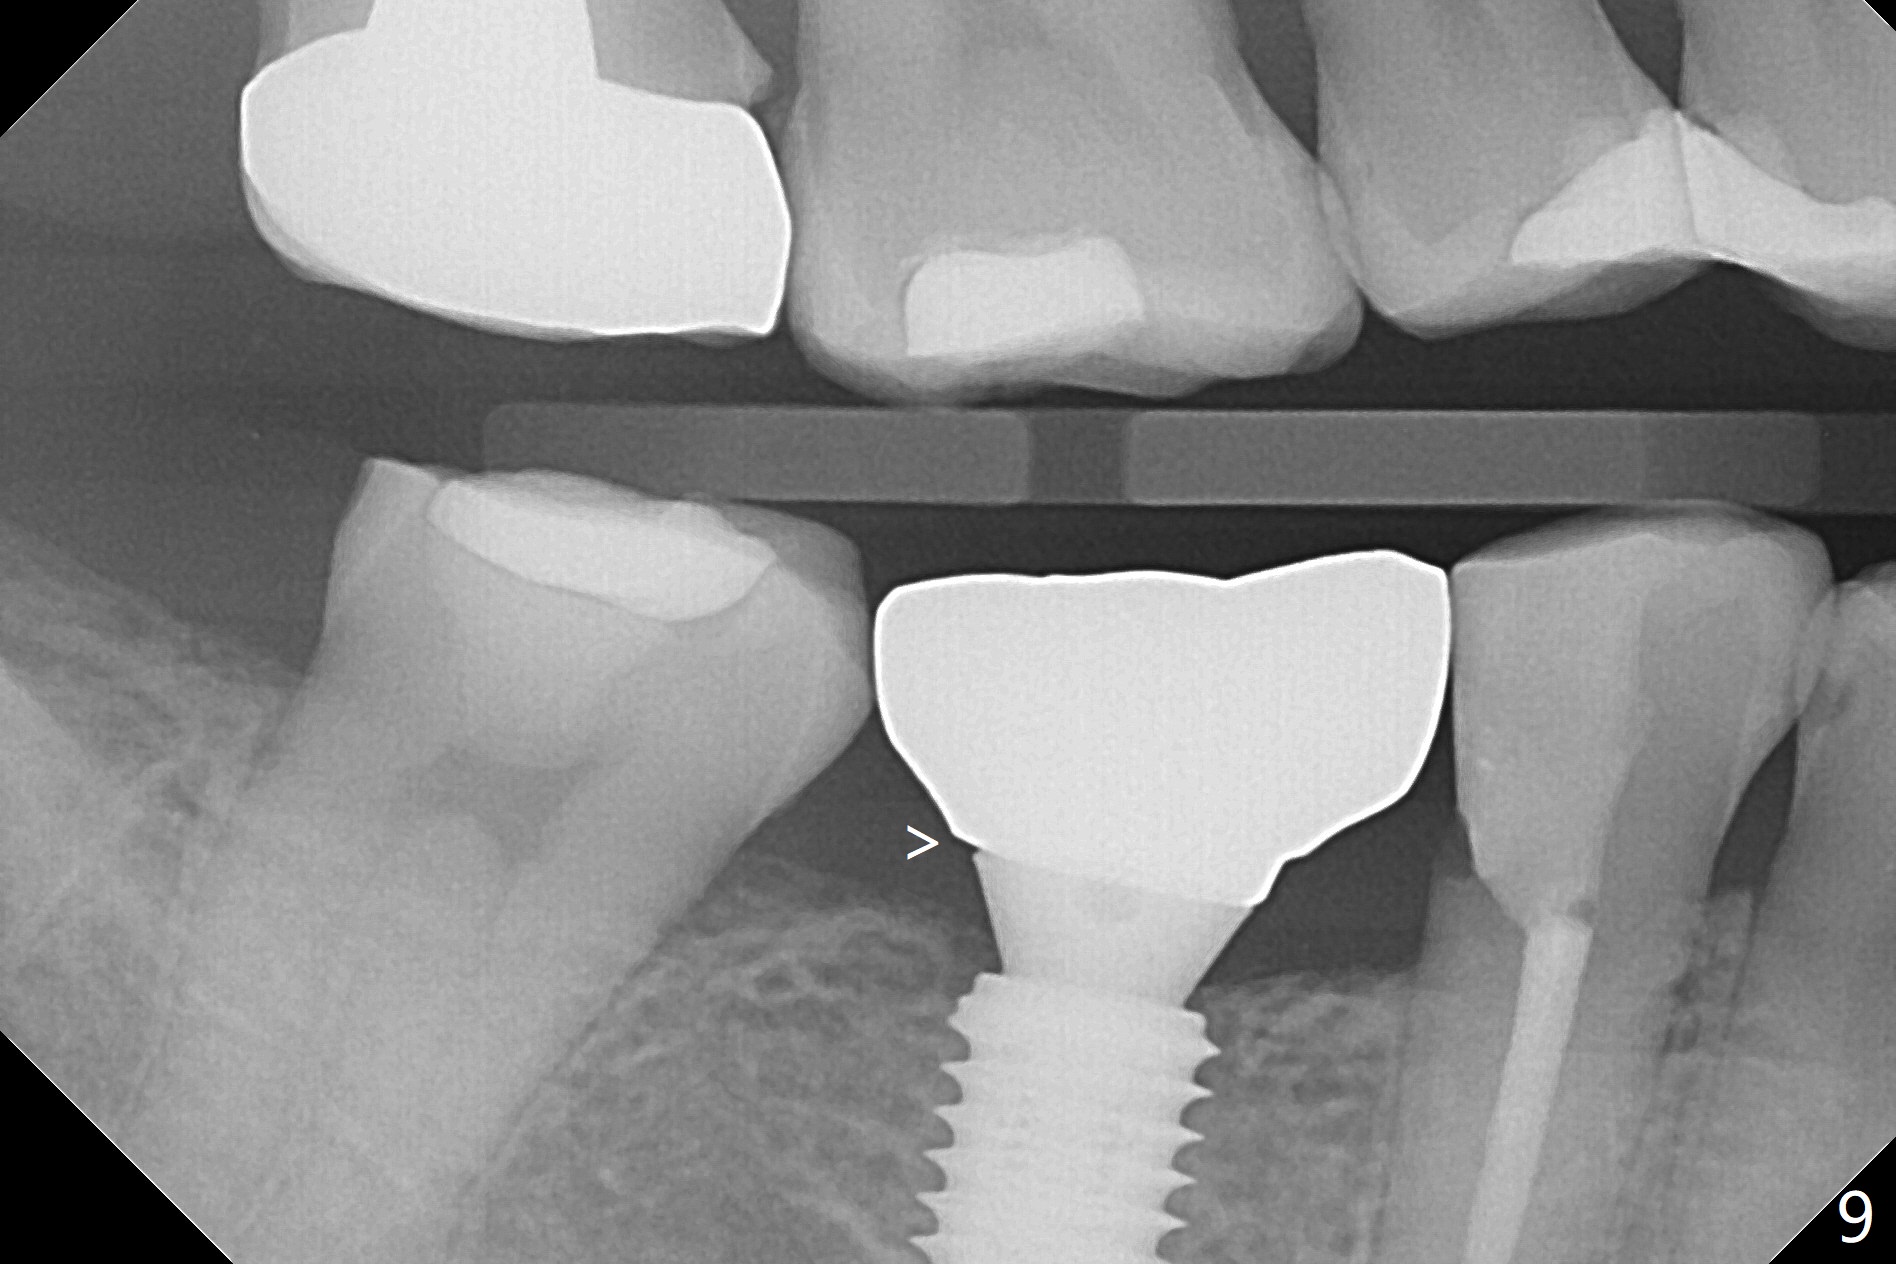

A 5x10 mm implant is placed at #30 with a surgical guide (Fig.1 *) in 10 minutes. The most amazing part of this surgery is that the guide allows you to place the implant at the precise level care-free (~ 1 mm subcrestal, Fig.2,3). Everything happens so quick that when a 5.5x3 mm healing abutment is placed (Fig.4), you are pleased to feel that the implant is stable (Fig.5). You could not ask for anymore. The fearful patient reports no postop pain. The implant is placed as planned (Fig.6, overlap image provided by the guide designer, Jennifer). The patient returns for impression nearly 2 months postop (Fig.7,8). It appears that the implant has osteointegrated without bone loss (Fig.7). The soft tissue is healthy around the just placed cementation abutment (Fig.8 (5.2x4(2) mm)). When the permanent crown is seated initially 2.5 months postop, the mesial contact is slightly tight and the occlusion is high. Bitewing shows the distal open margin (Fig.9 >). After mesial contact adjustment, the patient feels that the occlusion is better. With further occlusal adjustment, the crown is cemented without distal open margin (Fig.10). The patient returns to her home country for 3 months. The implant is doing well 3.5 months post cementation; impression is taken for #14 surgical guide.